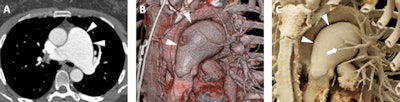

Images from an 87-year-old woman who presented for follow-up of mild aneurysmal dilation of the ascending aorta. A: Axial postcontrast 2D CT image demonstrates dilated vascular structures in the mediastinum (white arrowhead). B and C: Volume-rendered images demonstrate another of these dilated vascular structures (white arrowheads), which in 3D are more apparently aneurysms of the bronchial arteries. D-F: Cinematic-rendered images again demonstrate the multiple bronchial artery aneurysms (white arrowheads depict the aneurysm that arises at the origin of one of the bronchial arteries from the descending aorta). This patient was not felt to be a candidate for any therapy of these lesions given significant comorbidities, and no cause for the bronchial artery aneurysms was ever uncovered. Nonetheless, the realistic shadowing provided by cinematic rendering and that is most apparent in F provides very clear representation of the relationships between the aneurysms and other structures, including the heart and descending aorta, and would be of value in surgical planning.